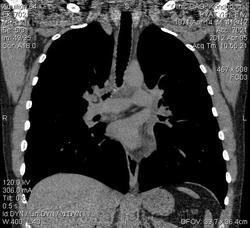

Слева легочный рисунок усилен за счет сосудистого компонента, равномерное утолщение стенок бронхов верхней и нижней долей с уменьшением их внутреннего диаметра, утолщение междольковых перегородок - интерстиц. отек? Увеличение объема клетчатки корня левого легкого и средостения - структура ее однородна, плотность от -5 до 5 HU. Жидкости в плевральной полости не выявлено. Имеется небольшой перикардиальный выпот.

тут нет интерстициального отека!!местами на ограниченном участке определяются участки утолщения междолькового интерстиция ,но основная масса-это центрилобулярные узелки и изолированные очаги в обоих легких.скорее всего это поствоспалительные изменения ,также необходимо исключить бронхиолит

интерстициальный отек ? мне кажестя наоборот постпневмонический  интерстициальный фиброз (утолщение междольковых септ , плеворпульмональные спайки)  Так же не согласна с уменьшением внутреннего диаметра бронхов. Наоборот субсегментарные бронхи нижней доли  слева расширены, что так же говорит о  фиброзных изменениях на фоне перенесенного воспаления. Стенки утолщены -да. Утолщена междолевая плевра слева.